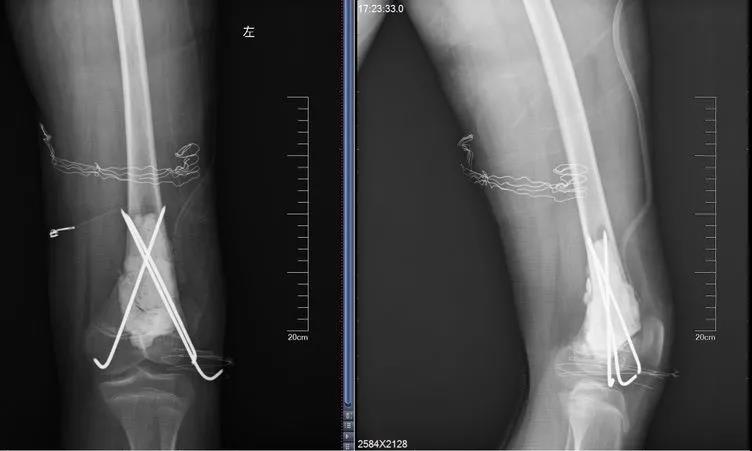

无独有偶,11岁的女孩儿晨晨,假期在家和小伙伴玩耍时,不慎摔倒,本来家长并未在意,但晨晨直喊疼,且大腿活动障碍。在当地医院检查确诊为左股骨中下段骨折,随后医生对病灶刮除,按照一般骨折处理。

当地医生将病理组织送河南省肿瘤医院病理会诊,提示为骨肉瘤。

最终,王鑫医师组为浩浩、晨晨两位小朋友选择了新辅助化疗,待疼痛症状缓解后,手术取出钢板、钢钉,并通过扩大切除手术,完整切除长瘤子部分的股骨,并进行体外灭活,搭配肿瘤型组配人工膝关节置换,达到了既完整切除肿瘤,又保全了孩子肢体功能的目的。